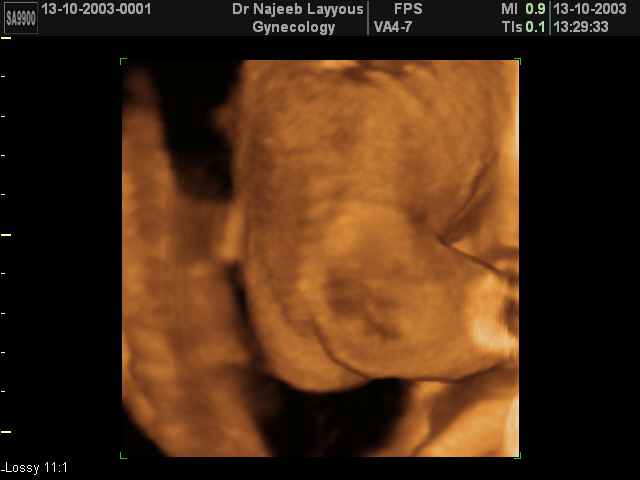

- صور لوجه الجنين في داخل الرحم

- صور جانبية لرأس الجنين

صور لأعضاء الجنين بجهاز الموجات فوق صوتية ثلاثي الأبعاد | الدكتور نجيب ليوس